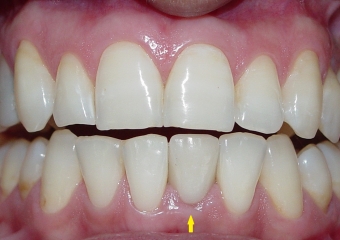

Imagens finais do caso terminado em fevereiro de 2010, com prótese em porcelana sobre implante